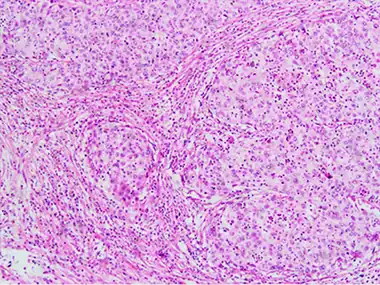

Invasive squamous cell carcinoma of the cervix is characterized by infiltration as irregular anastomosing nests or single cells.[64] This case is poorly differentiated. H&E stain.